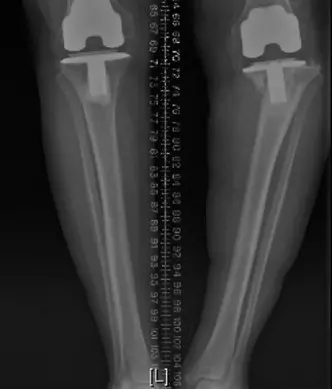

صورة توضيحية لـ ألم مفصل الركبة الصناعي: دليل شامل لتشخيص وعلاج التهاب وارتخاء المفصل الصناعي